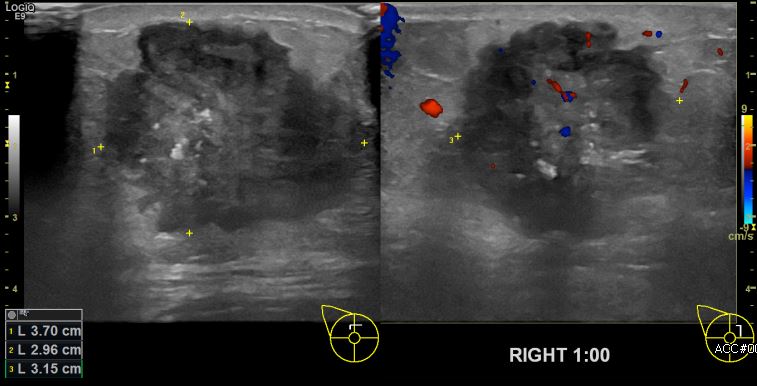

상기환자 우측 유방의 멍울로 내원하신 60대 여성분으로 본원초음파상 우측 1시 방향에

의심스러운 멍울 조직검사 시행하여 우측 침윤성 유관암 진단되었습니다.